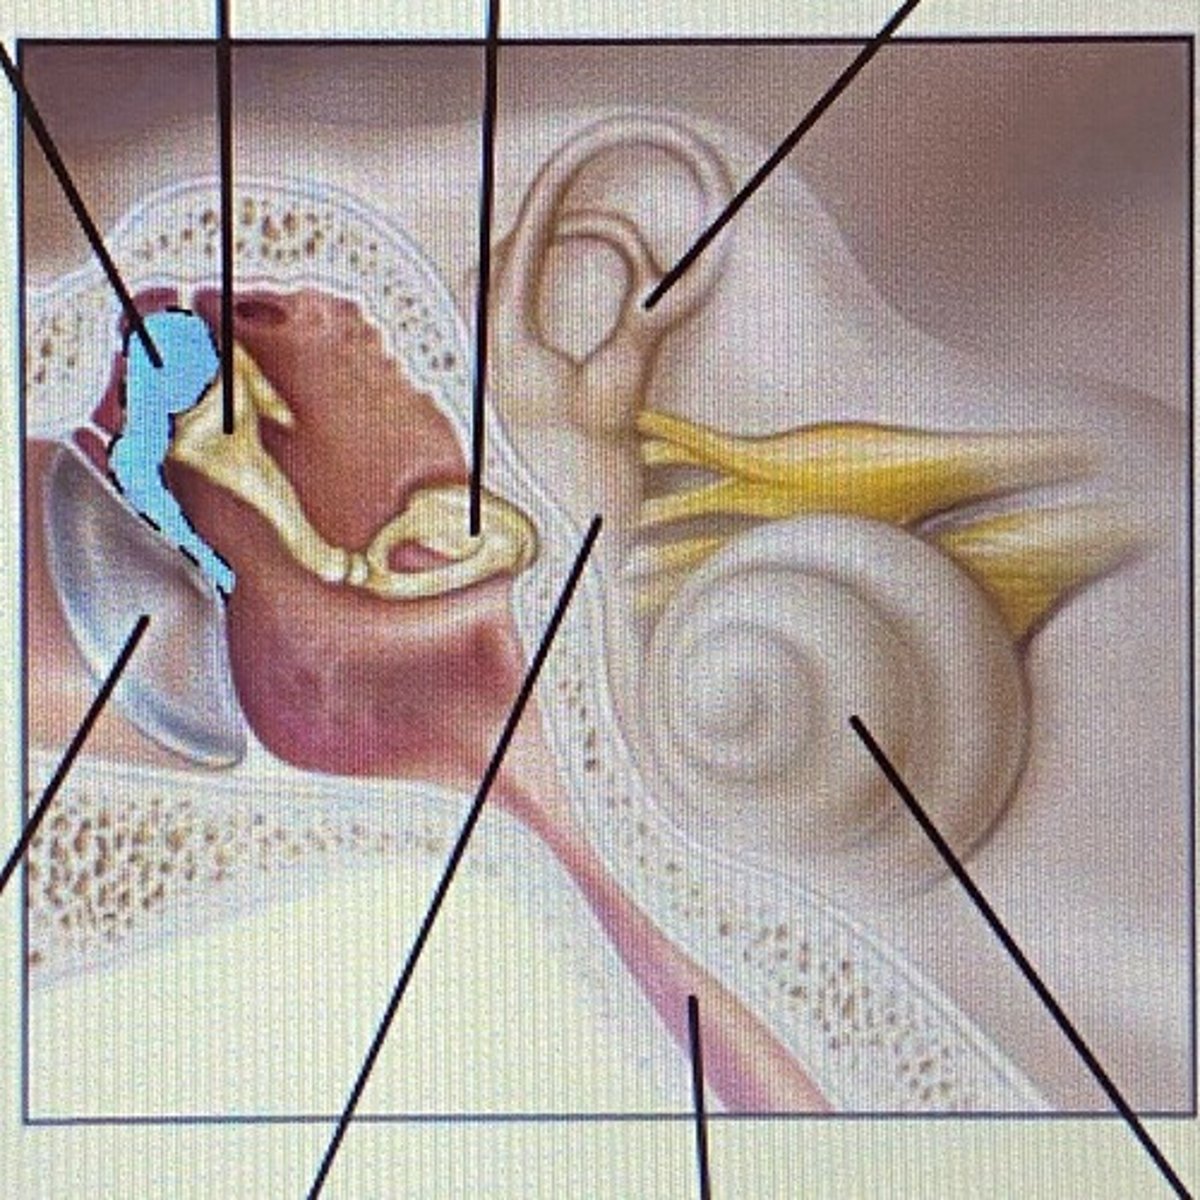

auricle

External Acoustic Meatus

vestibule

-functions in balance and equilibrium

Vestibulocochlear Nerve

- cranial nerve 8

Stapes

Incus

Malleus

Tympanic Membrane

pharyngotympanic tube

external ear

middle ear